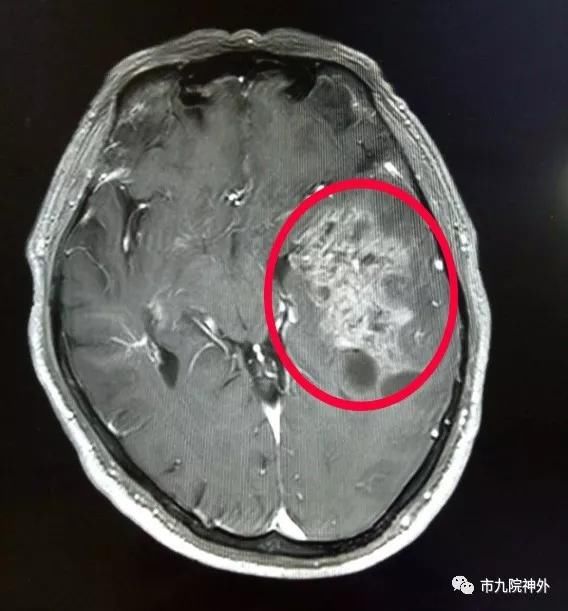

术前头颅MRI:肿瘤位置

行头颅MRI检查,结果显示:左侧颞叶病变。结合孙先生目前已出现的头痛、头晕、记忆力下降等症状,需进行切除手术治疗,而合理的手术入路方式是从患者左侧颞叶入路,手术过程中如何尽可能全切肿瘤又避免颅内血肿、损伤功能区、侧裂静脉及下引流静脉等,成为本次手术治疗的难点。